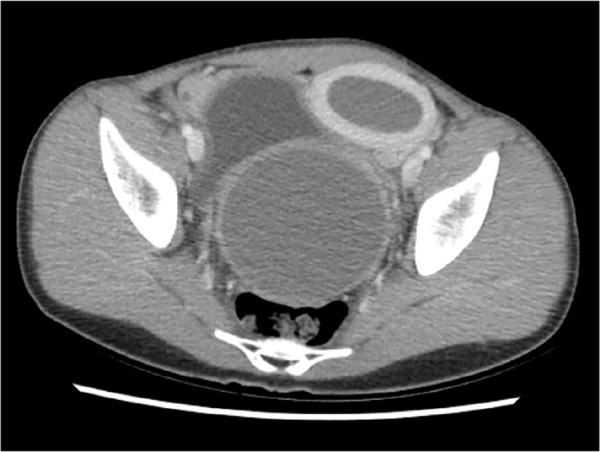

Physical examination revealed a tender, palpable mass protruding against her abdominal wall. Computed tomography of the abdomen and pelvis identified the mass as the uterus and vagina, which were both markedly distended with fluid (Figure 1). Magnetic resonance imaging confirmed single uterine and vaginal cavities without abnormal divisions. The cervix and ovaries appeared normal (Figure 2 and Figure 3).